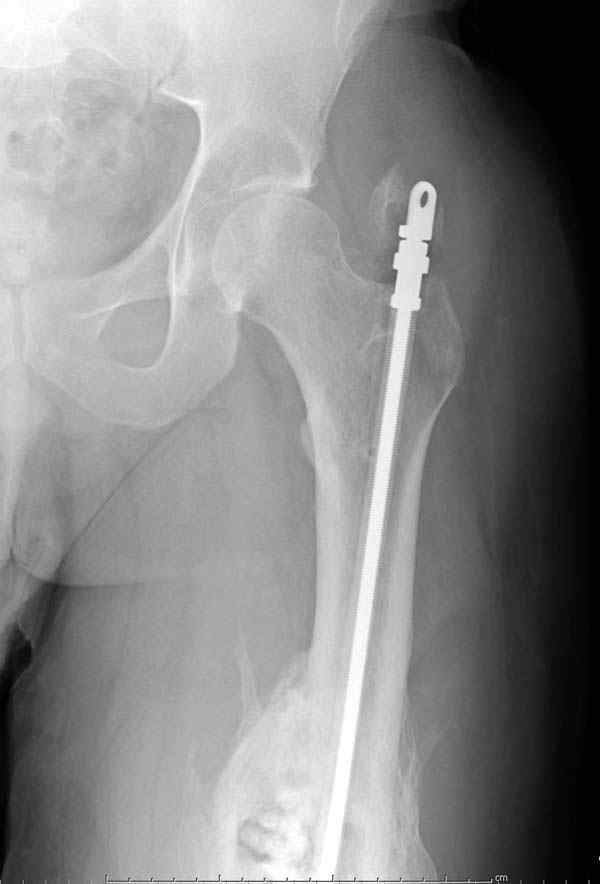

Недавний случай: год назад леченный интрамедуллярным гвоздем открытый перелом бедра инфецировался, многократные Irrigation&Debridment

закончили вставлением антибиотического гвоздя и кожной пластикой переднего мягкотканнего дефекта.

На ренгенограмме явный остеомиелит с секвестром, секвестерэктомия из медиального доступа и замена старого антибиотического гвоздя на новый.

ренгенограмма инфицированного бедра со старым

антибиотическим гвоздем